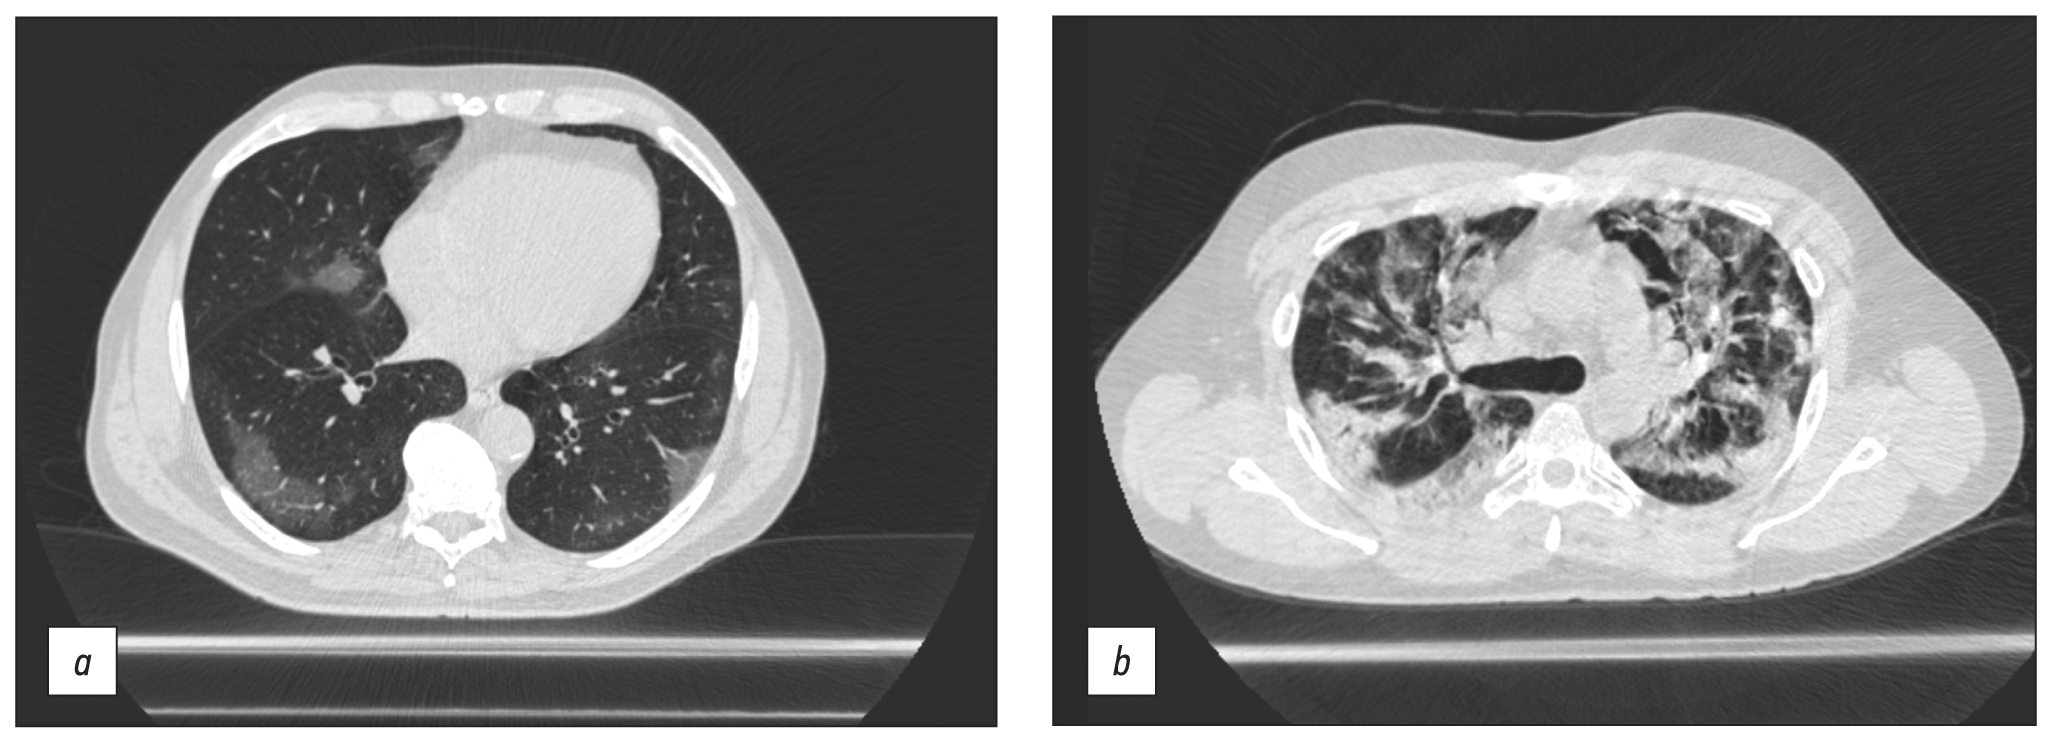

Chest CT was conducted in the majority of cases to obtain a diagnosis or to provide continuing observation for patients with COVID-19 pneumonia. The scanning parameters (Table 1) enable us to obtain images of adequate quality to differentiate between viral pneumonia, cardiogenic pulmonary edema, and bacterial pneumonia. Fig. 5 shows CT data for COVID-19-associated viral pneumonia patients.

Fig. 5. Axial computed tomographic slices of chest organs in the lung window: (a) polymorphic, predominantly subpleural areas of ground-glass opacity, corresponding to the CT image of viral pneumonia (including COVID-19), CT-1, and (b) multiple polymorphic areas of parenchyma compaction with a tendency to merge, with ground-glass opacity areas and mild reticular changes, CT-3.

A mobile CT generated acceptable quality chest CT images detecting viral pneumonia (see Fig. 5 a), and the patient capacity was sufficient for a temporary hospital with 1,300 beds in overload circumstances. The peak load was 110 scans per day, with an average of 44. This system differs from modular and mobile CTs mounted on trailers [7], mostly due to the use different types of CT.